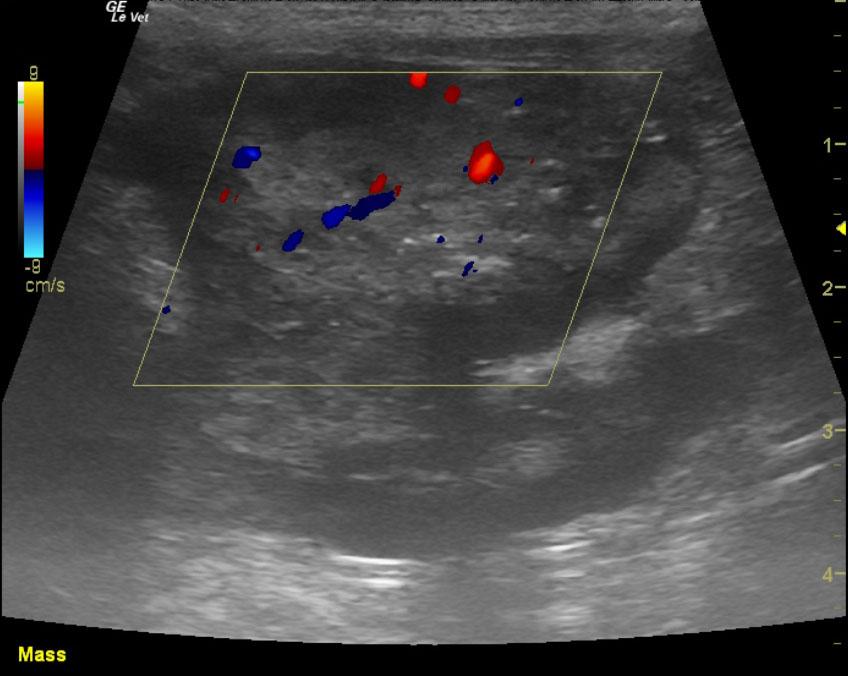

An 16 year-old NM DSH was presented for evaluation of small kidneys and an abdominal mass. Urinalysis showed an inappropriate urine specific gravity (1.014). CBC was within normal limits but elevated creatinine was present on serum biochemistry.